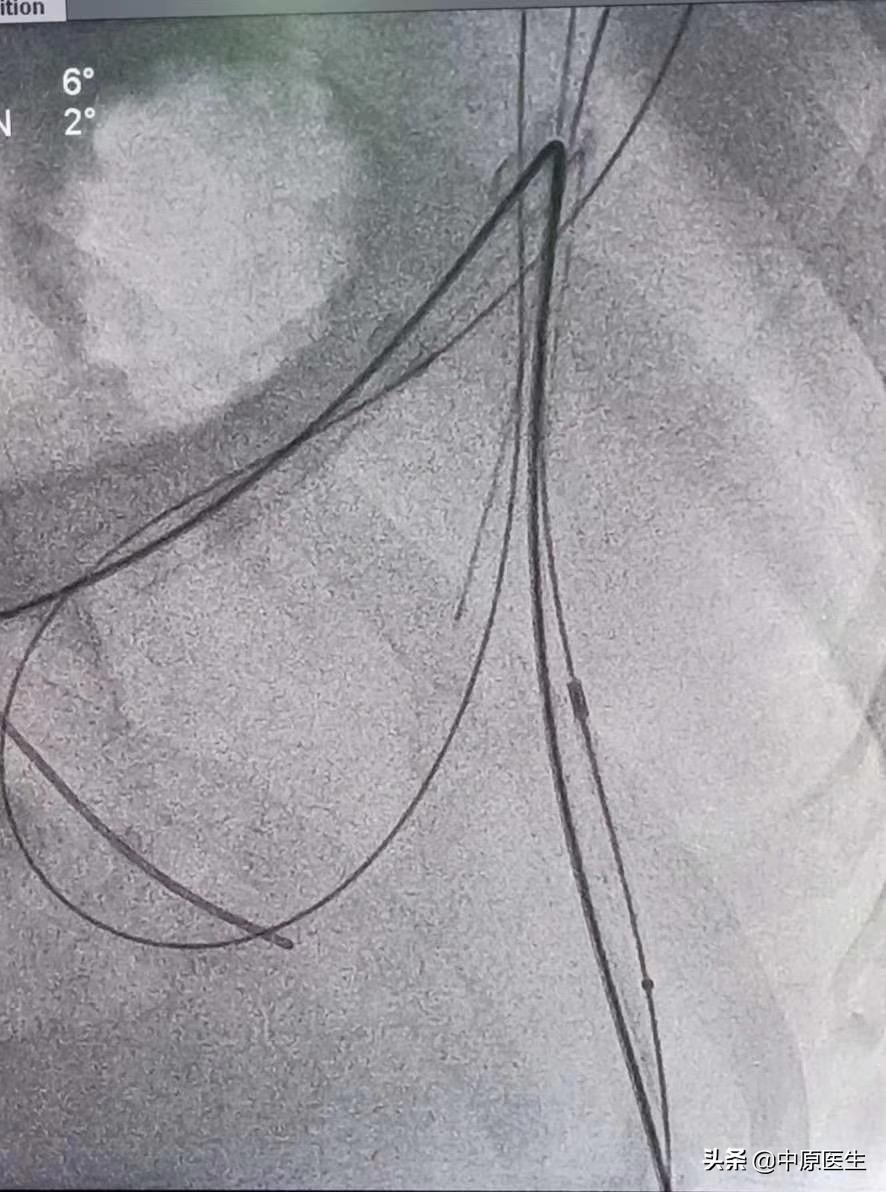

经过会诊,我们介入科刘建文教授团队决定通过介入方法帮助患者解决肿瘤引起梗阻的问题。25日,在导管室行局麻下消化道造影+降结肠球囊扩张+经肛型肠梗阻导管置入术。术中透视见腹部膨大,肠管明显扩张,膈肌上移。让患者取截石位仰卧,充分润滑、局麻后,我们送入超滑导丝、直径不到1mm的导管,反复尝试导丝通过闭塞处、送至横结肠脾曲处,但导管无法跟进,为了保留150cm的超滑导丝,将100cm的直径不到1mm导管分段剪断、依次撤出,再送入直径2mm的指引导管,再送入一根260cm的超滑加硬导丝,送至横结肠内,依次用10mm球囊、肠梗阻导管的扩张器反复扩张狭窄处,肠梗阻导管仍无法通过,再次同轴送入双导丝,应用16mm球囊多次扩张后,顺利把肠梗阻导管送至横结肠内,充盈导管头端球囊,将肠梗阻导管头端固定于降结肠梗阻处上方;淤积的肠气和部分肠液、粪便排入引流袋内,病人腹胀减轻。术中反复交换各种导丝、导管,带出不少臭屁、臭粪便。整个手术间都是不可描述的气味、手术台不忍直视。

这是刘建文、李陆鹏医生在完成12台手术后,迎来的最后一台手术。体力、精力都消耗很大。连年轻体壮的李陆鹏(大鹏)累的都受不住了,这台手术,刘建文医生吃射线透视时间102:49分。